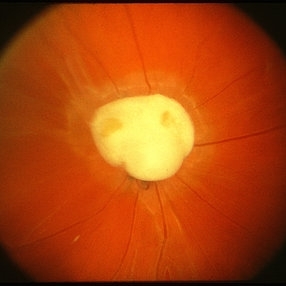

Toxocara granuloma of the optic nerve head.

Condition/keywords: ocular toxoplasmosis, toxocara granuloma, toxocariasis